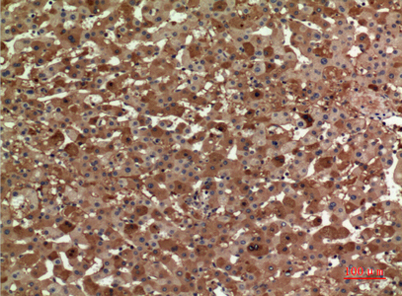

Product name: ApoA-I rabbit pAb

Dilutions: Western Blot: 1/500 - 1/2000. IHC-p: 1/100-1/300. ELISA: 1/20000. Not yet tested in other applications.

Immunogen: The antiserum was produced against synthesized peptide derived from the Internal region of human APOA1. AA range:81-130